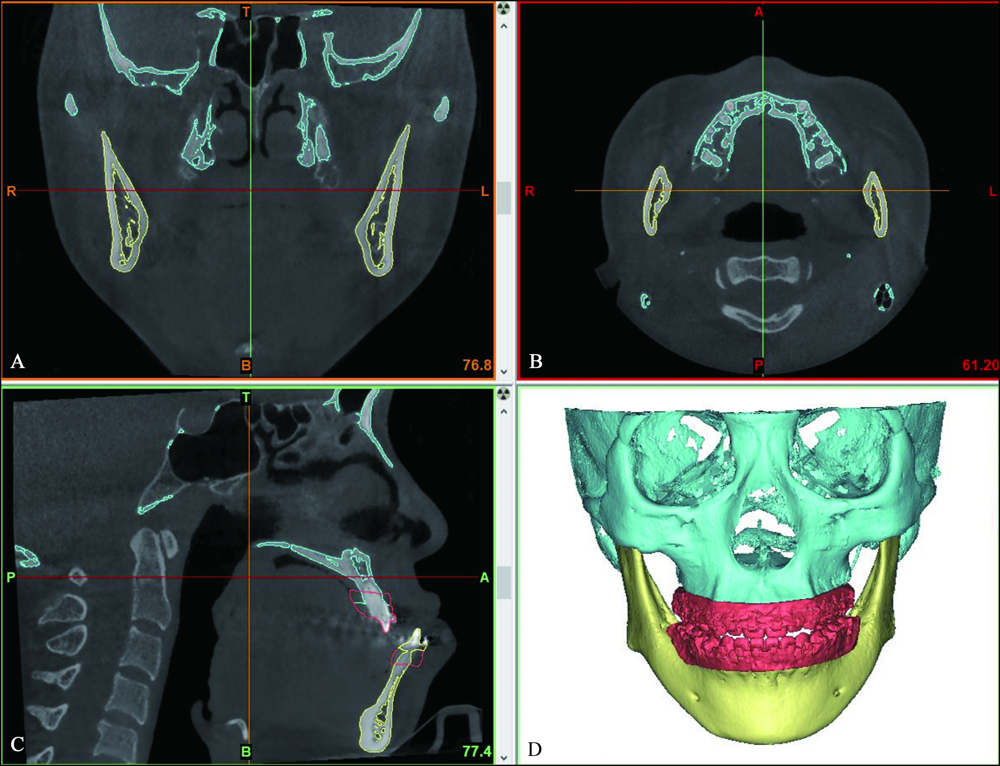

图1

ProPlan CMF 1.4中三维重建的上下颌骨模型 A:冠状面;B:水平面;C:矢状面;D:上下颌骨三维模型。"